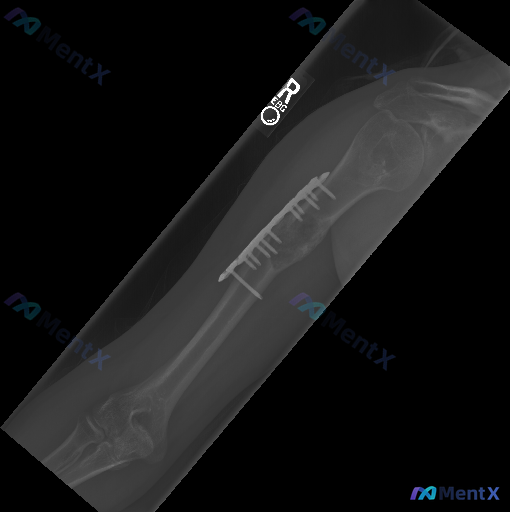

整理到一个右前臂尺桡骨骨折术后的影像学病例,资料如下: 基本背景 右侧前臂(桡骨与尺骨)双骨折术后内固定状态。 影像学表现 1. 内固定:桡骨、尺骨干均可见钢板+螺钉固定,钢板跨越骨干中段,目前钢板螺钉位置固定,未见明显移位、松动或断裂征象。 2. 骨折愈合:骨折断端处骨痂形成尚不明显(骨痂影较淡)...